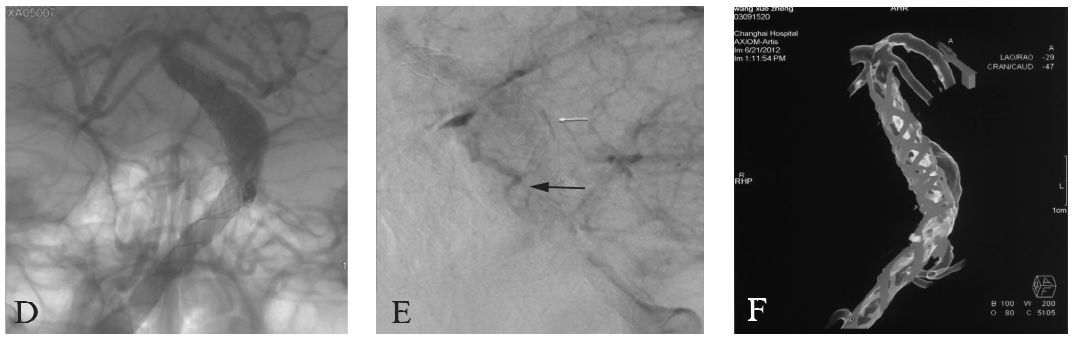

MRI:头颅MRI平扫显示椎基底动脉均增粗,基底动脉偏向左侧并超过鞍背外侧,基底动脉桥脑水平从左侧压迫脑干,脑干无明显水肿。T₂WI可见增粗的基底动脉内有血栓形成(图16-1A)。

CTA:椎基底动脉明显增粗,以右侧椎动脉为优势椎动脉,双侧椎动脉硬化,椎基底动脉汇合处明显向左侧偏移,基底动脉中下段可见梭形动脉扩张(图16-1B)。

DSA:前后位的右侧椎动脉造影显示右侧椎动脉及基底动脉增粗,基底动脉中下段管腔膨大,椎基底动脉明显向左侧偏移(图16-1C)。

图16-1椎基底动脉冗长扩张症患者术前影像学检查

A:MRI平扫T₂WI轴位示基底动脉血管腔内血栓形成;

B:CTA三维成像(后前位观);

C:椎基底动脉冗长扩张症血管造影图像